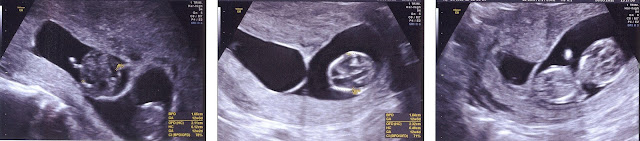

Before I go on, I have to say HUGE thanks to Dr. Shivani and the team at SCI. They have made our dreams come true and everyone there was very great to work with as we went through the formalities following the birth of Sebastian and Sienna. Our wonderful surrogate has also been amazing. We'll never forget what she has done for us and she'll be a part of our family stories for the rest of our lives. If it wasn't for her nearly nine months of dedication, this wouldn't have been possible: